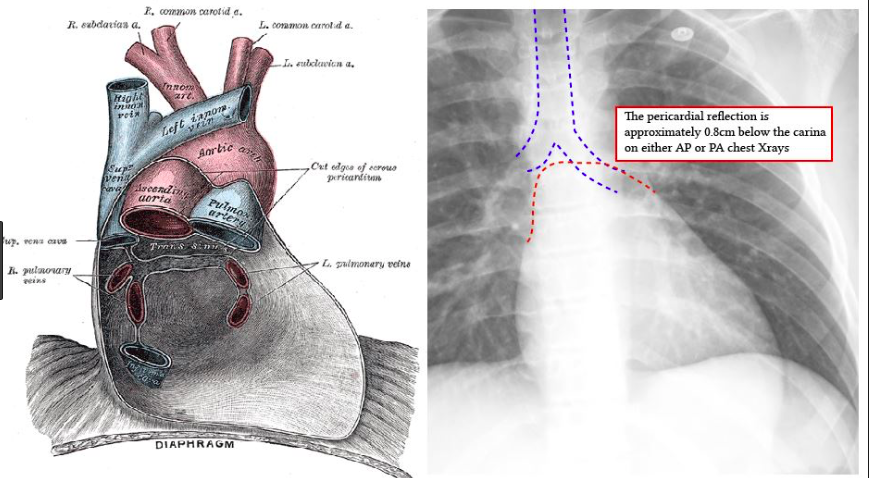

Screen Shot 2018-08-31 at 5.00.29 PM Published August 31, 2018 at 869 × 478 in VIVA AID: IDEAL POSITION OF TIP OF RIGHT IJV CATHETER Next →